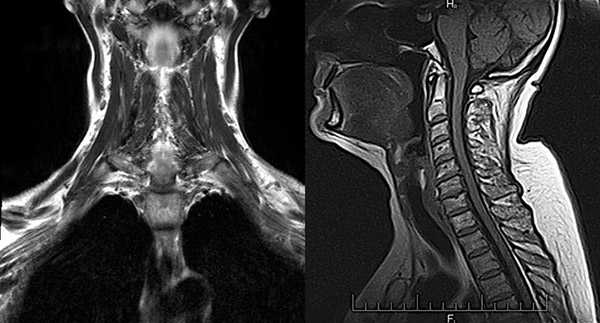

КТ, МРТ при добавочной слюнной железе в поднижнечелюстном пространстве

Для выявления болезней слюнных желез (сиалоаденит, синдром Шегрена, закупорка протоков камнями) применяются лучевые методы - КТ, МРТ, УЗИ. Специфичность компьютерной томографии при нозологических формах около 100%, достоверность - 98%. Показатели высокие для достоверной верификации патологии околоушных, подчелюстных желез. Ограничивает повсеместное применение метода радиационное облучение. Разовая обследование не приносит вреда, но не рекомендуется делать сканирование часто (за исключением верификации новообразований).

МР-томография хорошо дифференцирует изменения железистых структур. Стоимость оборудования и техническое обслуживание высокое. Установлены аппараты в крупных мегалополисах, что снижает доступность исследования для населения.